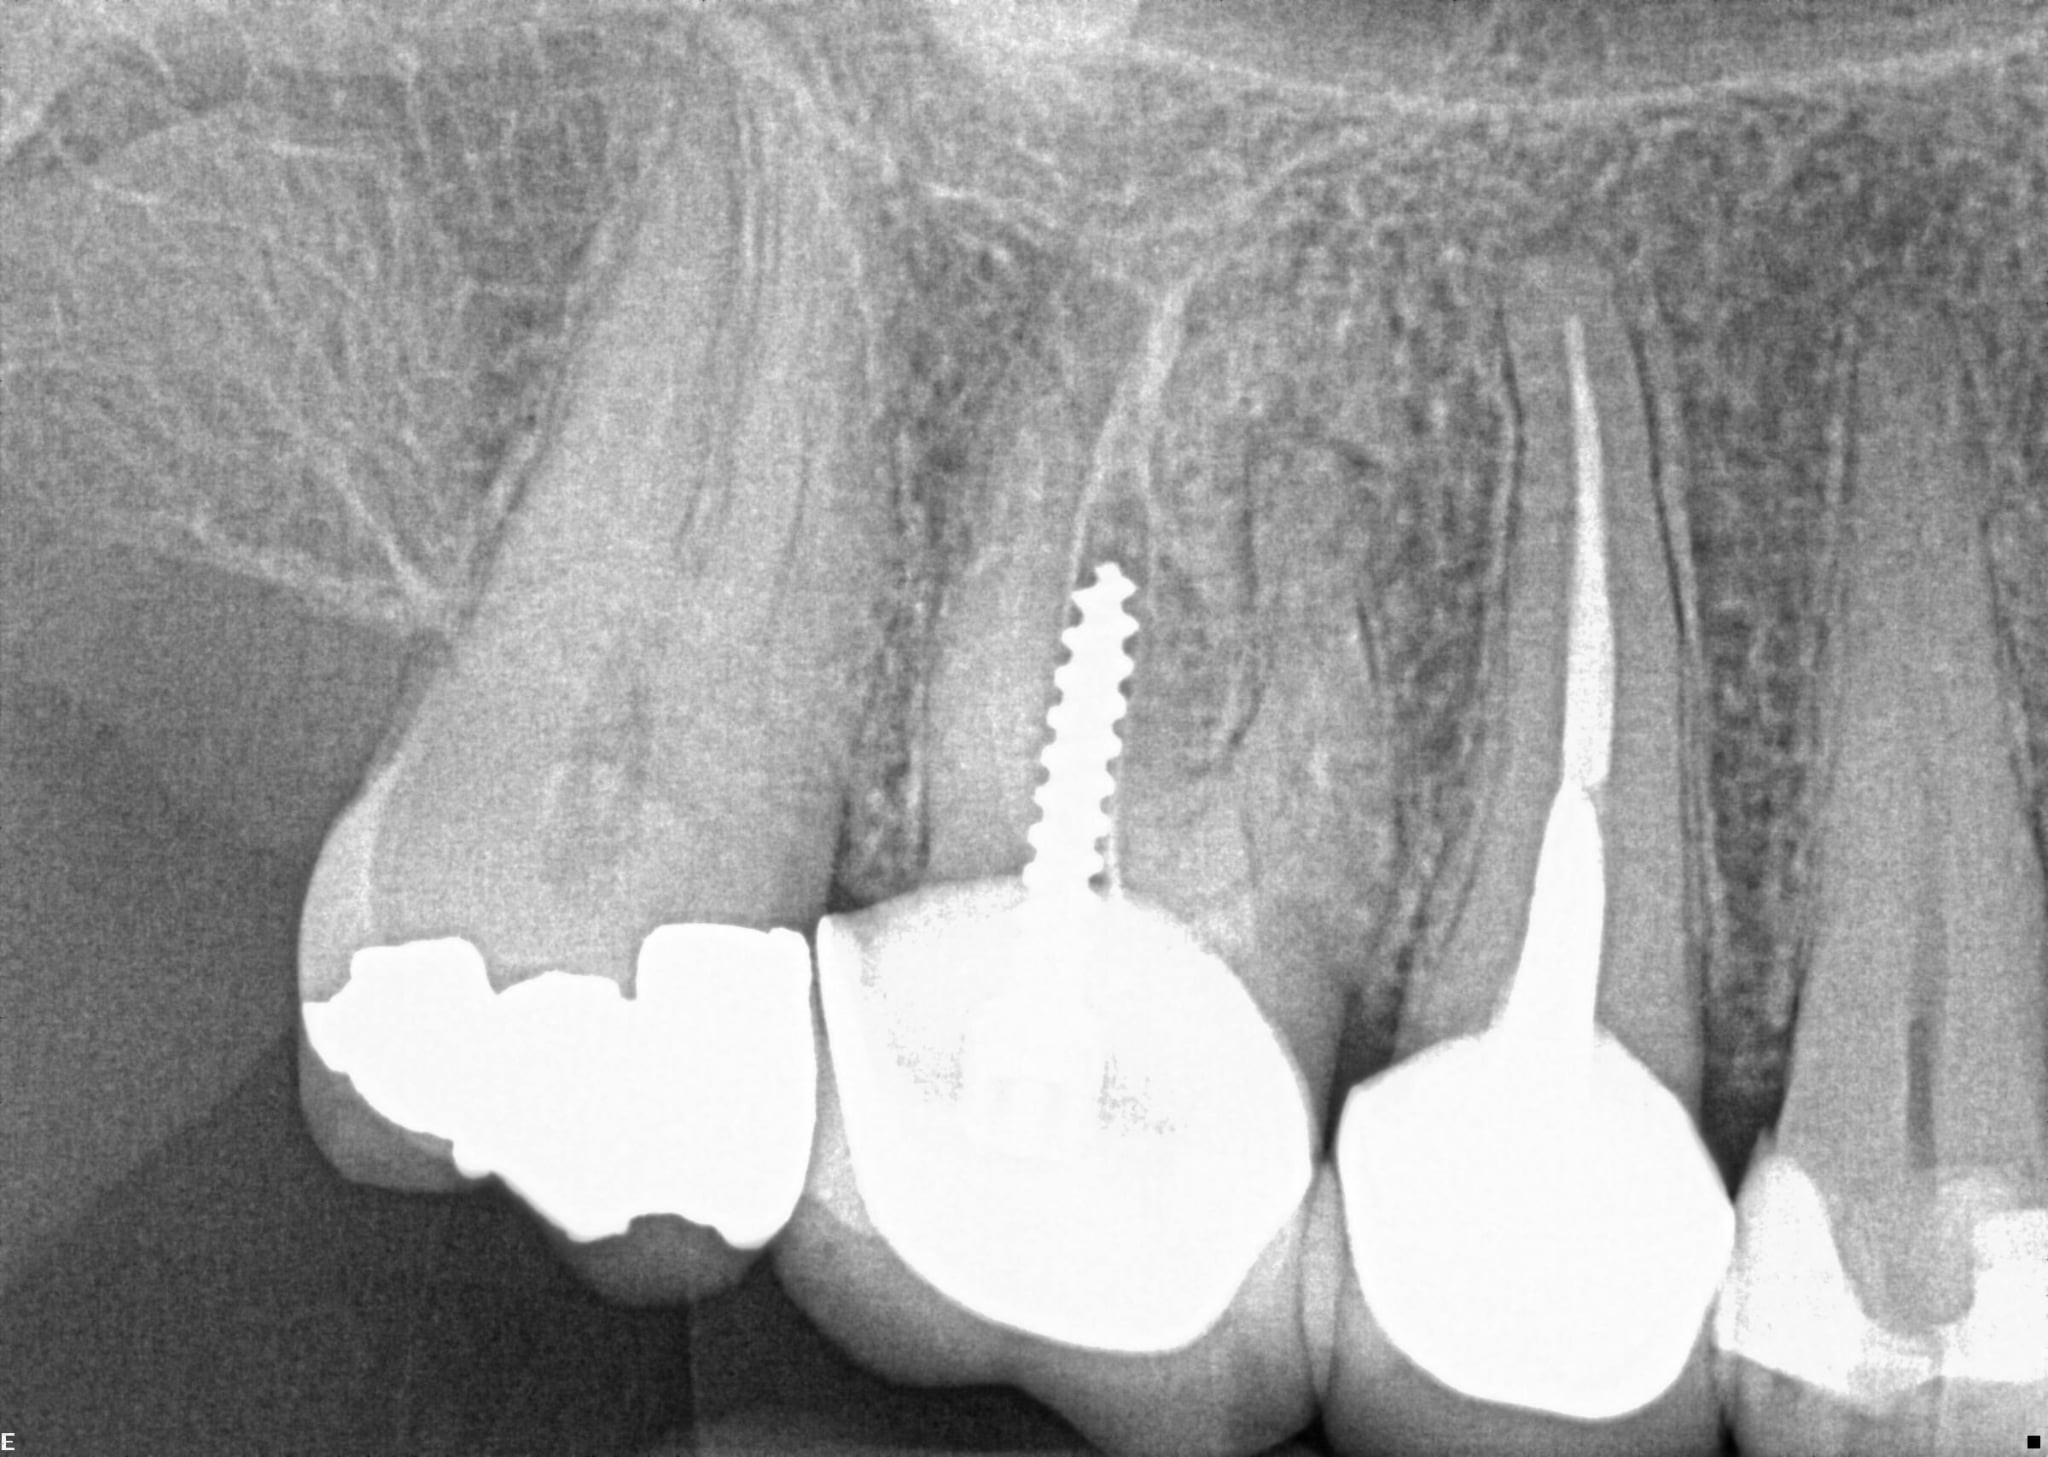

3. What option can describe the post placement in the X ray bellow for the tooth # 3.6?